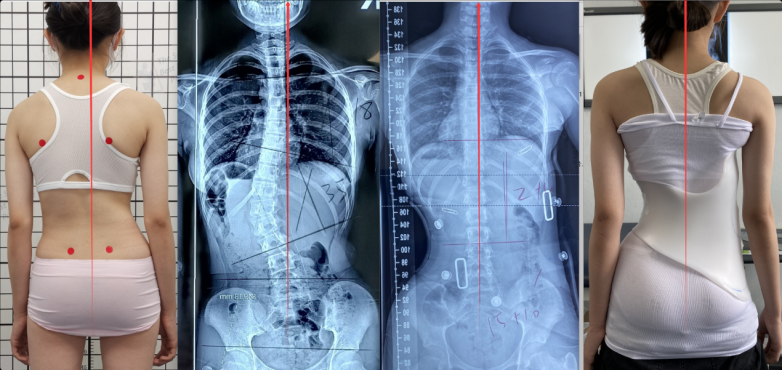

这种过矫正不仅体现在Cobb角的度数上,更体现在躯干的整体对称性。临床数据显示,GBW支具的即时入具矫正率往往能超过50%,甚至达到80%-90% 。

GBW支具案例